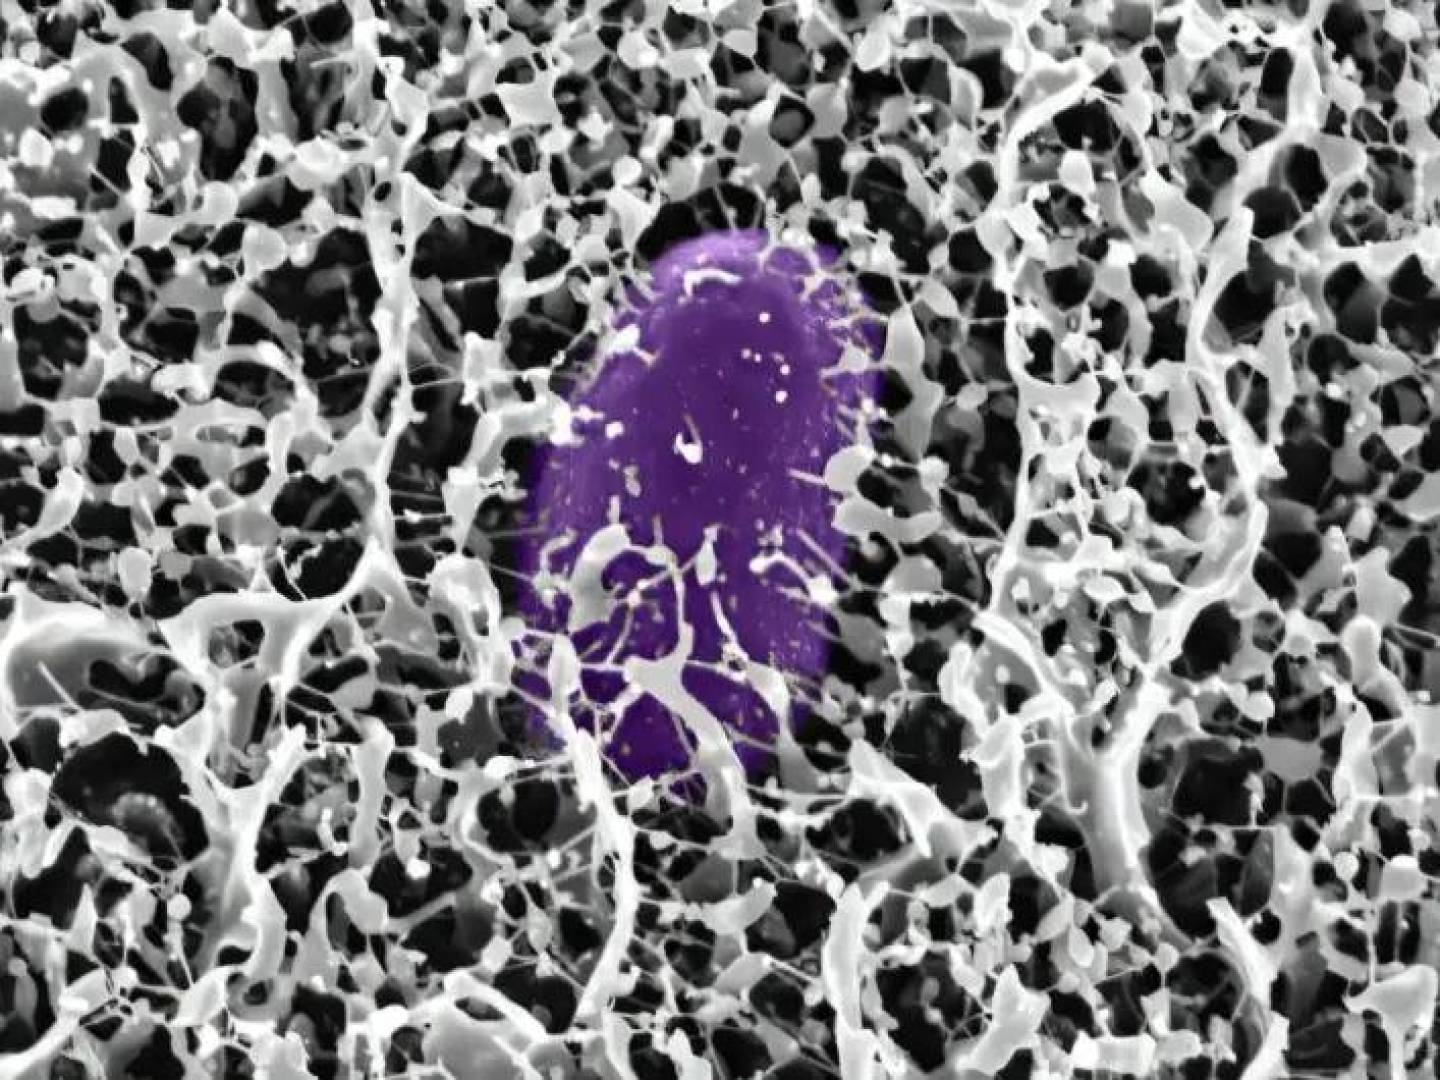

يعرف العسل بخصائصه العديدة المضادة للبكتيريا والالتهاب، وحسب دراسة أجريت لبحث فعالية علاج تقرحات الفم بالعسل موضعيًا، تم وضع العسل على تقرحات الفم لدى مجموعة من المرضى 4 مرات في اليوم لمدة 5 أيام، كما تم تطبيق كلٍ من علاج الكورتيكوستيرويد الموضعي والمخدر الموضعي بنزوكاين على مجموعات أخرى من المرضى.

وجدت هذه الدراسة أن علاج تقرحات الفم بالعسل يعد امنًا وفعالًا في تقليل حجم القرحة ومدة الألم وحرارة القرحة. [مرجع]

ومن الجدير بذكره أنه لا يتساوى كل العسل في الفعالية والفوائد، إذ إن معظم أنواع العسل الموجودة تجاريا تتعرض للتعقيم في درجات حرارة عالية مما يؤدي لتدمير معظم العناصر الغذائية الموجودة فيها، والعسل غير المبستر وغيرالمصفى مثل عسل المانوكا يكون أقل معالجة ومحتفظًا بخصائصه العلاجية.[مرجع]